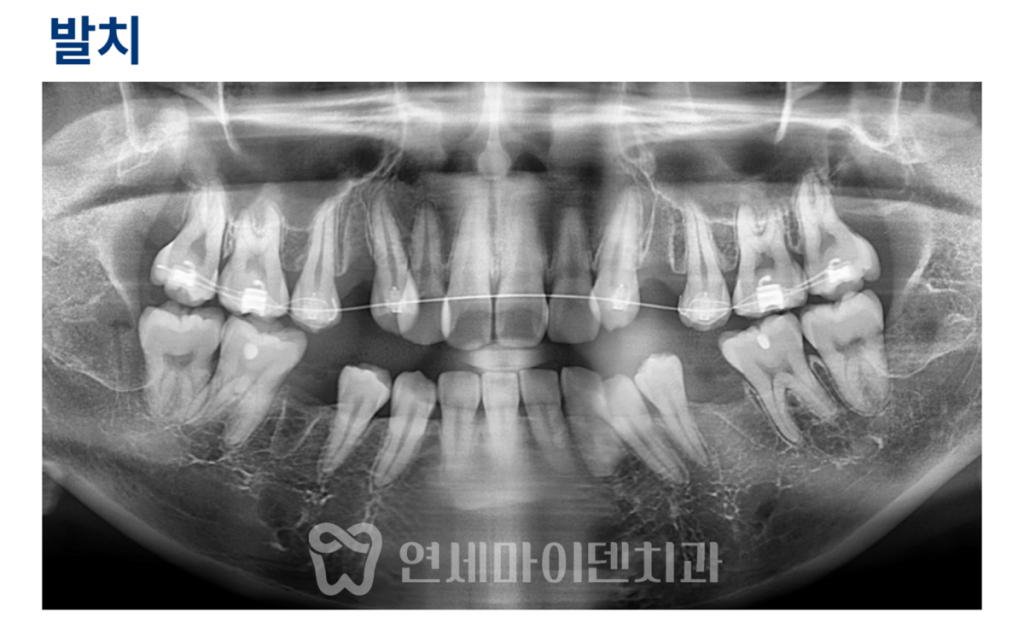

치아교정 계획 수립

상악은 송곳니의 중복 배열로 인해

발치가 불가피한 상태였고,

하악 역시 악궁 개선과 배열 교정을 위해

발치를 계획했습니다.

발치 위치는

상악은 제1소구치,

하악은 제2소구치를 선택했습니다.

또한 어금니를 위쪽으로 끌어올리는

함입 치료를 병행하여

위아래 치아가 맞물릴 수 있도록

수직 교합을 조정하는 계획을 세웠습니다.

치료 중간 과정 (7개월 차)

필요한 발치를 먼저 시행한 후,

윗턱에서는 송곳니 뒤쪽 치아부터

교정 장치를 부착해 송곳니 정렬을 우선 진행했습니다.

송곳니 위치가 안정된 이후

앞니까지 장치를 확장해

전체 치열을 정리하는 방식으로 진행했습니다.

치료 7개월 차에는

발치 공간이 점차 닫히기 시작했고,

치아 배열도 눈에 띄게 정돈되었습니다.

상악 어금니 함입을 위해

안쪽과 바깥쪽에 미니스크류를 식립하고,

고무줄을 이용해 위쪽으로 이동시키는 치료를 병행했습니다.

이 과정에서

그동안 닿지 않던 위아래 치아가

점차 맞물리기 시작하는 변화가 관찰되었습니다.